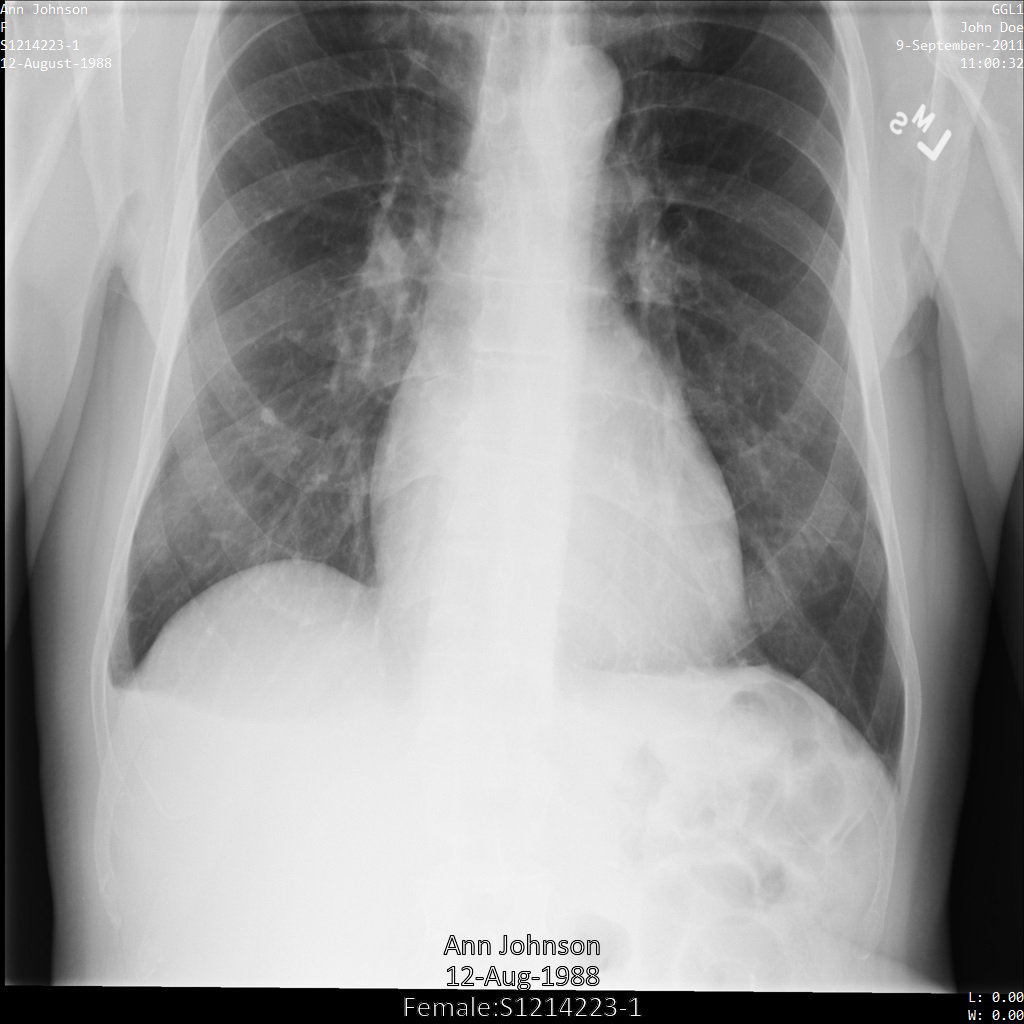

サンプル画像

このページの一部のサンプルには、匿名化された画像の出力が含まれています。各例では、入力として以下の元画像を使用しています。各匿名化オペレーションからの出力イメージをこの元のイメージと比較して、オペレーションの効果を確認できます。